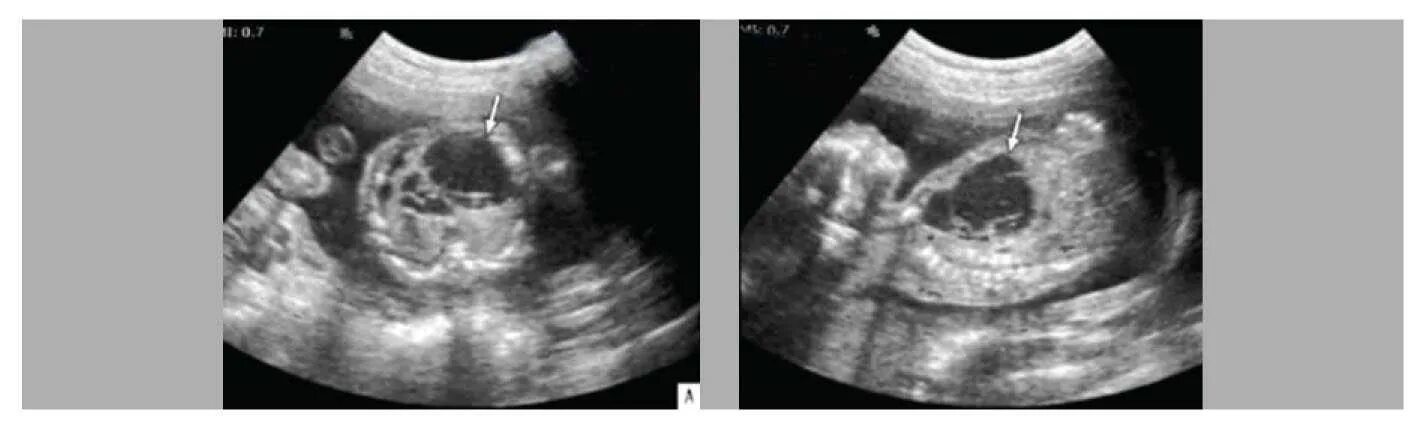

Узи аномалий